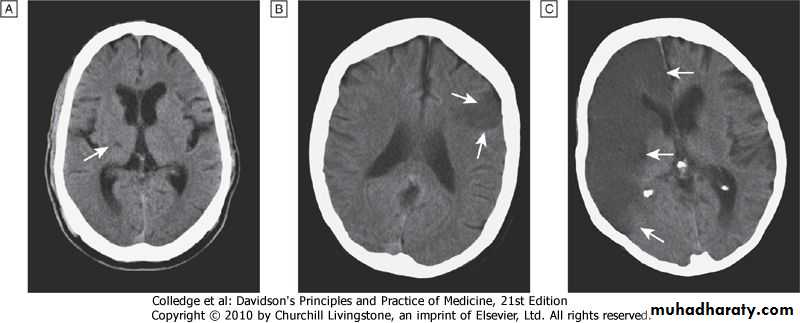

3-CNS

3-Central nervous systemBV+PARENCHYMA

1-Stroke -2- Carotid atheroma + transient cerebral ischaemic attacks.

3- Subarachnoid haemorrhage

4-Hypertensive encephalopathy

high blood pressure+ neurological symptoms,

Papilloedema is common.

CT scan = haemorrhage in and around basal ganglia

neurological deficit = usually reversible

if hypertension is properly controlled